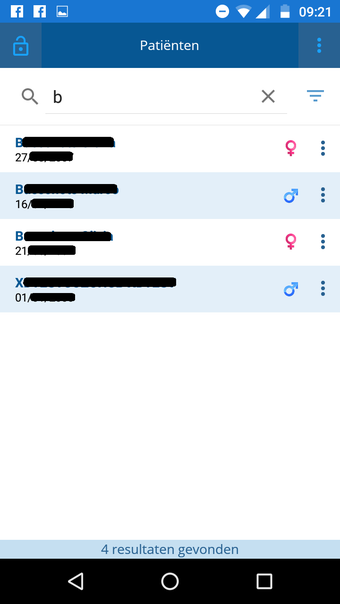

CoZo est une application de santé électronique qui permet aux patients et aux médecins de communiquer entre eux et de partager des informations médicales. Elle a été développée pour répondre aux problèmes du système de santé actuel, caractérisé par un manque de communication entre les patients, les médecins et les autres professionnels de la santé.

CoZo permet aux patients de prendre une part active dans leur propre santé et d'être traités comme des participants actifs dans le processus de soins. Les patients peuvent utiliser l'application pour enregistrer leurs données de santé, qu'ils peuvent ensuite partager avec leurs médecins. Les médecins peuvent utiliser l'application pour enregistrer l'historique médical de leurs patients, poser un diagnostic et suggérer un plan de traitement.